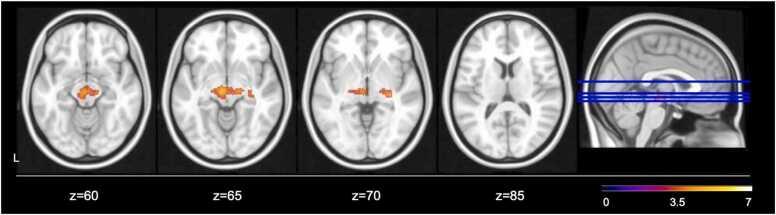

Earlier pubertal development appears to be one pathway through which childhood trauma contributes to psychopathology in adolescence. Puberty-related changes in neural networks involved in emotion processing, namely the amygdala-medial prefrontal (mPFC) circuit, may be a potential mechanism linking trauma and adolescent psychopathology. Our participants were 227 youth between 10 and 13 years of age who completed assessments of threat and deprivation-related experiences of adversity, pubertal stage, and internalizing and externalizing symptoms. A subset (n = 149) also underwent a functional MRI scan while passively viewing fearful and calm faces. Potential mechanisms linking childhood trauma with psychopathology, encompassing earlier pubertal timing and neural response to aversive stimuli were explored. Earlier pubertal development was associated with childhood trauma as well as increased externalizing symptoms in boys only. Earlier pubertal timing in males and females was negatively associated with activation in bilateral amygdala, hippocampal, and fusiform regions when comparing fearful and calm faces. However, amygdala-mPFC connectivity showed no association with pubertal timing or psychopathology symptoms. These findings do not support accelerated amygdala-mPFC development as a mechanism linking childhood trauma and psychopathology, but instead provide support for the role of pubertal development in normative decreases in limbic activation across development.

早期的青春期发育似乎是童年创伤导致青少年精神病理学的途径之一。与青春期相关的神经网络变化,涉及情绪处理的杏仁核-内侧前额叶(mPFC)回路,可能是将创伤和青少年精神病理学联系起来的潜在机制。我们的参与者是 227 名 10 至 13 岁的青少年,他们完成了与威胁和剥夺相关的逆境经历、青春期阶段以及内化和外化症状的评估。一小部分(n=149)还接受了功能磁共振成像扫描,同时被动地观察恐惧和平静的面孔。探索了将儿童期创伤与精神病理学联系起来的潜在机制,包括青春期提前和对厌恶刺激的神经反应。青春期提前与童年创伤以及男孩的外化症状增加有关。男性和女性的青春期提前与比较恐惧和平静面孔时双侧杏仁核、海马体和梭状回的激活呈负相关。然而,杏仁核-前额叶皮层连接与青春期时间或精神病理学症状没有关联。这些发现不支持加速的杏仁核-前额叶皮层发育作为将儿童期创伤与精神病理学联系起来的机制,而是支持青春期发育在正常情况下减少边缘系统激活的作用。